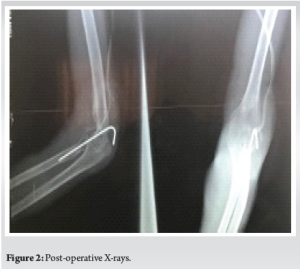

Removal of the fibrosis and ossifications permitted us to reduce the dislocation, which was maintained by a condylo-radial Kirschner pin with a flexed elbow at 90° (Fig. 2). An intraoperative fluoroscopy control was done using a C arm image intensifier and the vascular examination was normal.